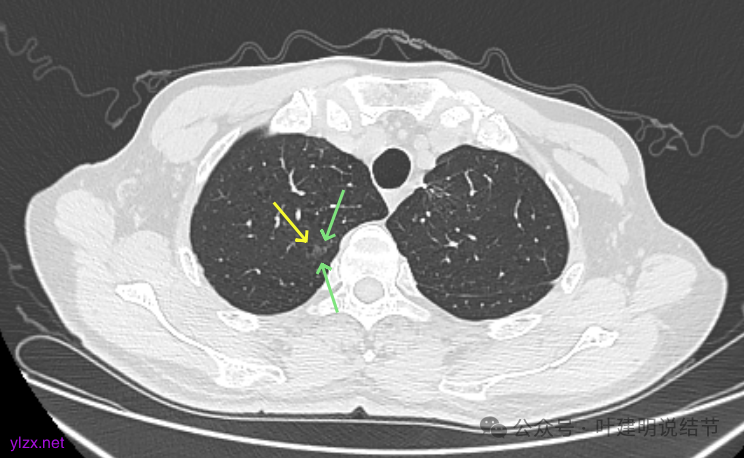

再看2022年9月的:

右上病灶此层面偏长条,密度较低。

左上已经手术。

左上另有一处磨玻璃结节,由于手术后结构变化,此灶是术前哪处感觉不太好对比。